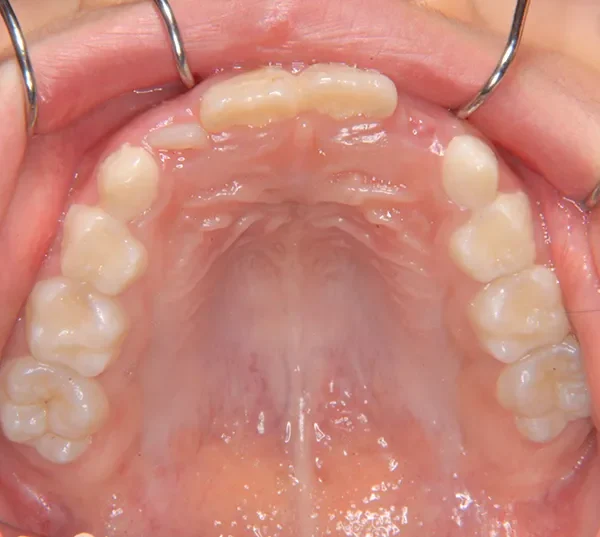

【子供の矯正(一期)】叢生・反対咬合・受け口・非抜歯症例・7歳女児【M.H様】

初診時年齢 小学校1年生 (女性) 主訴 受け口

診断名 叢生・反対咬合 装置名

状態 永久歯が生える隙間がない(叢生)

受け口(下顎前突/反対咬合)

下顎が大きい傾向があります。

上下の真ん中にズレがあるのと、上下とも永久歯の生えるスペースがせまいため、オリジナル矯正装置でスペースを作り、受け口も改善していきます。